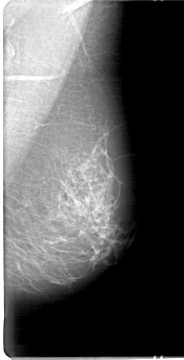

D_4027_1.LEFT_CC

LEFT_CC LINES 5296 PIXELS_PER_LINE 2536 BITS_PER_PIXEL 12 RESOLUTION 43.5 NON_OVERLAY